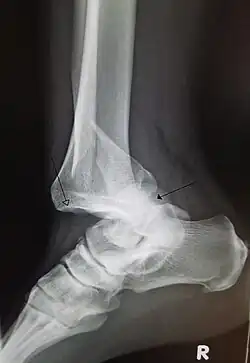

A traumatic dislocation of the tibiotarsal joint of the ankle with distal fibular fracture. Open arrow marks the tibia and the closed arrow marks the talus.

• Foot and Ankle

• Ankle sprains primarily occur as a result of tearing the ATFL (anterior talofibular ligament) in the talocrural joint. The ATFL tears most easily when the foot is in plantarflexion and inversion. Weakening of the ligaments can put the ankle at risk for dislocation.[50]

• An ankle dislocation without fracture is rare, due to the strength of ligaments surrounding the ankle.[51]